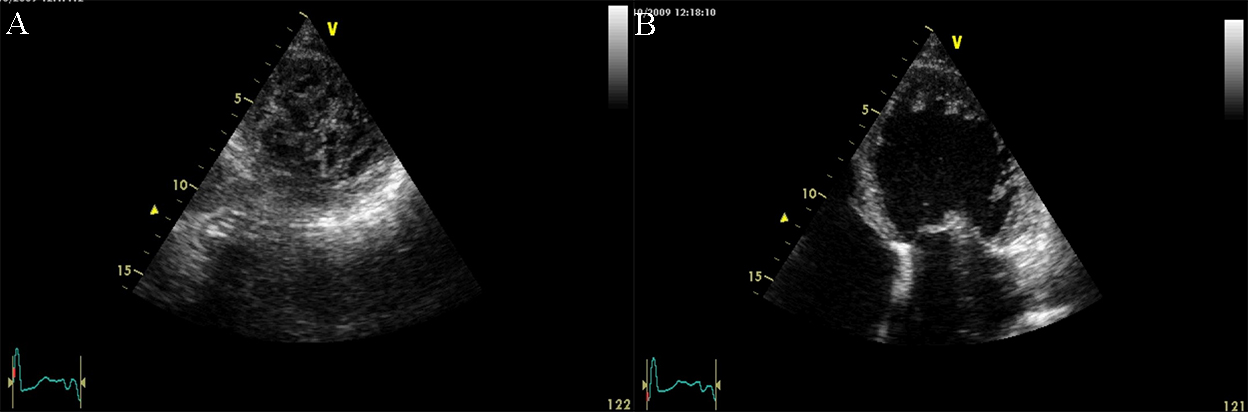

The initial imaging evaluation comprises of two main 2D echocardiography parameters: left ventricle ejection fraction (LVEF) less than 40% or fractional shortening less than 25% [6]. However, the comprehensive diagnosis of DCM should consider aspects of the clinical presentation, patient examination and other test results. Dilatation of the LV, especially end-diastolic and end-systolic transverse diameter enlargement (spherical remodeling), associated with reduced wall thickness, is easily recognized with 2D echocardiography in parasternal long-axis view (See Fig. 1 and Appendix Video 1).

Fig. 1.Echocardiographic aspect of DCM. Parasternal long-axis view showing a dilated left atrium and left ventricle in diastole. An online video of this patient with idiopathic dilated cardiomyopathy is available (Appendix Video 1).

Fig. 2.Echocardiographic aspect of DCM in a patient with idiopathic dilated cardiomyopathy. (A) Parasternal short axis at the level of the mitral valve, diastolic frame showing a dilated left ventricle. (B) Parasternal short axis at the level of the mitral valve, systolic frame showing the small difference between the end-diastolic and end-systolic diameter of the left ventricle due to reduced contractility.